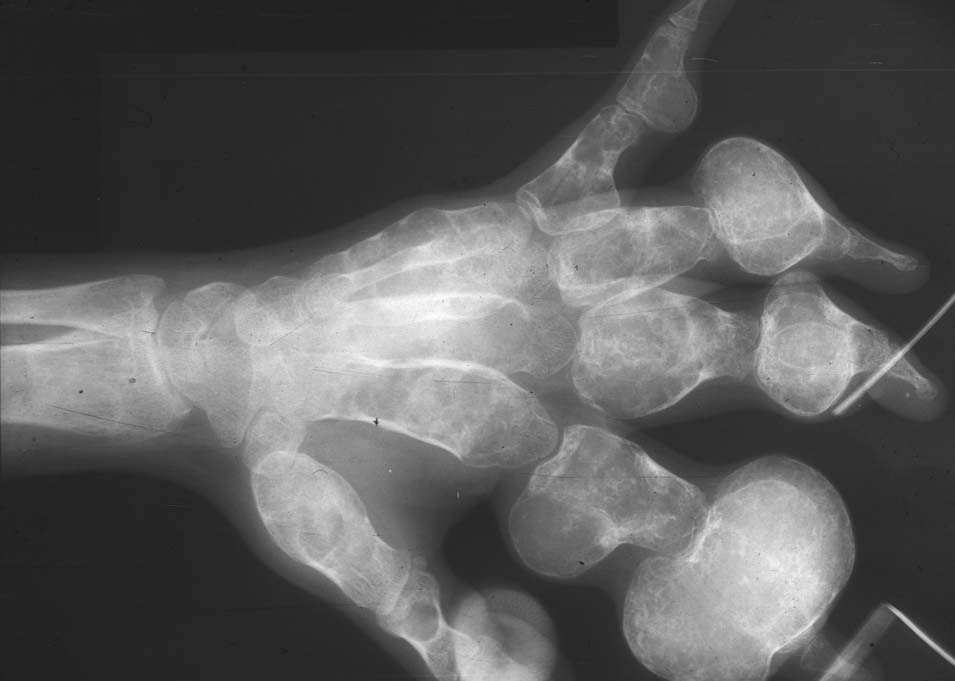

Визуальные материалы, связанные с болезнью Горхема-Стаута

Раздел: Альбом открытий